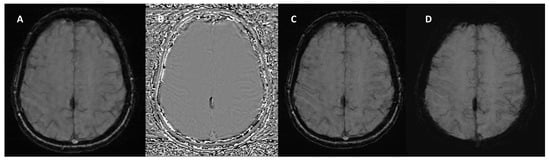

3. Technical Fundamentals of SWI